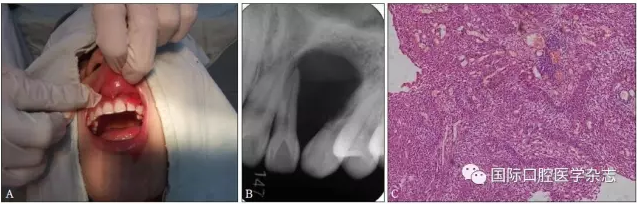

典型病例4 患者因左上頜牙齦長包塊就診,X線片檢查發(fā)現(xiàn)左上頜22—23牙區(qū)明顯的透射區(qū),邊界清楚,相鄰牙根被推擠移位。手術(shù)切除后病理結(jié)果為成釉細(xì)胞瘤(圖4)。

A:術(shù)前臨床照片;B:術(shù)前X線片;C:蘇木精-伊紅染色切片,顯示成釉細(xì)胞瘤的病理特點(diǎn) × 100。

圖 4 成釉細(xì)胞瘤